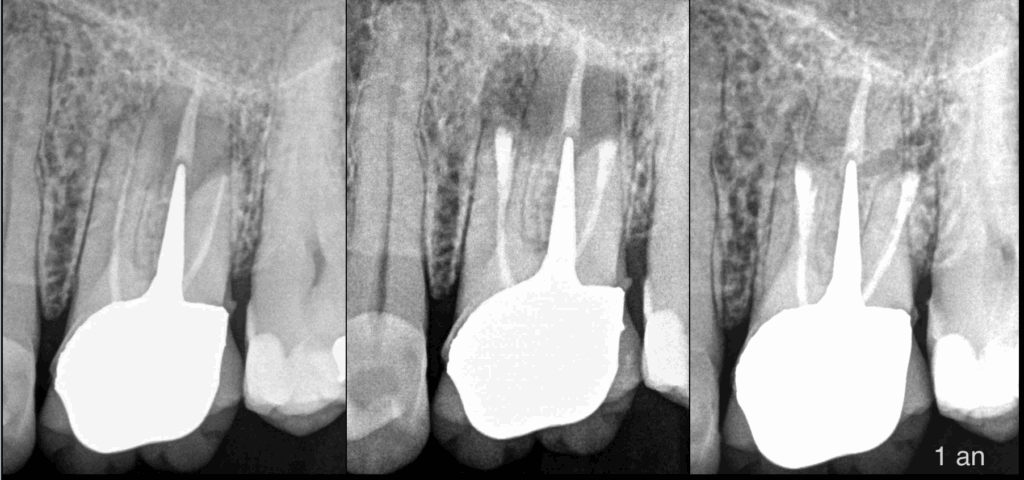

🔍 Un aspect dont on ne parle pas assez concernant la chirurgie endodontique : 𝐥𝐚 𝐩𝐫𝐞́𝐬𝐞𝐫𝐯𝐚𝐭𝐢𝐨𝐧 𝐛𝐢𝐨𝐦𝐞́𝐜𝐚𝐧𝐢𝐪𝐮𝐞 𝐪𝐮𝐢 𝐞𝐧 𝐫𝐞́𝐬𝐮𝐥𝐭𝐞 ! 🦷✨